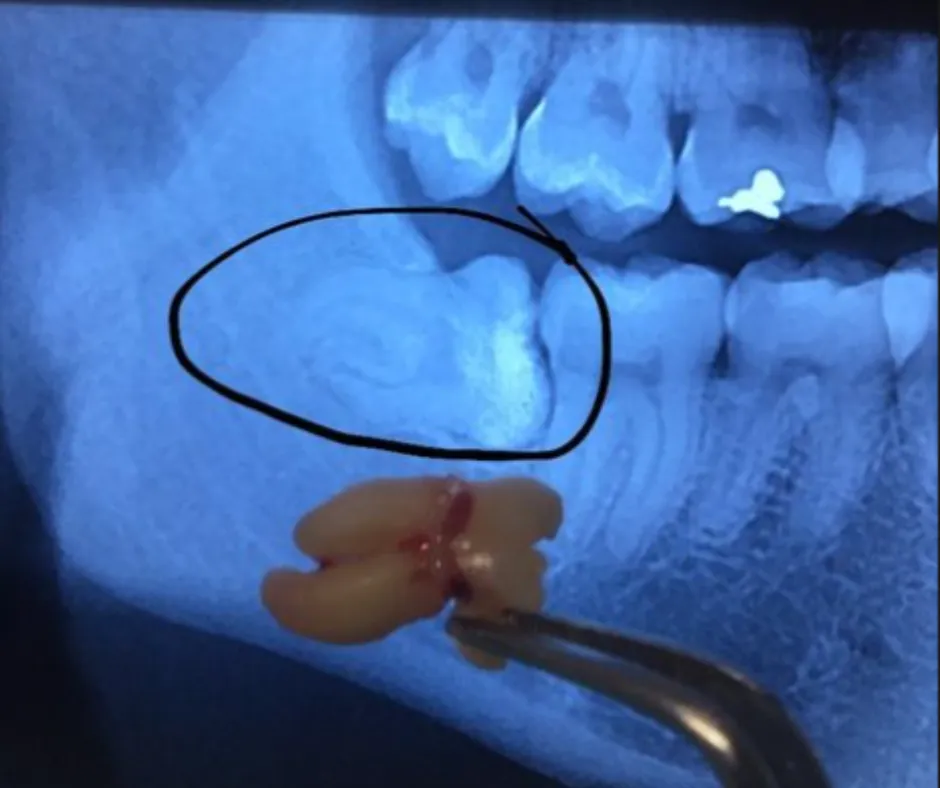

Vemos exactamente dónde están raíces, nervios y posición real.

Confirmamos si realmente necesitas la extracción y qué tan compleja será.

Radiografía panorámica.

Explicación clara de tu caso (con la imagen en pantalla).